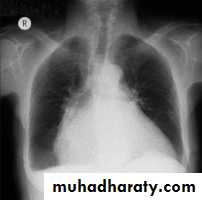

Radiology of the Heart

Lung fields:Congestion & edema in patients with left heart failure

Increased blood flow (prominent arteries and veins) in shunt lesions

Oligemic lungs in pulmonary stenosis

Pleural effusions in advanced heart failure